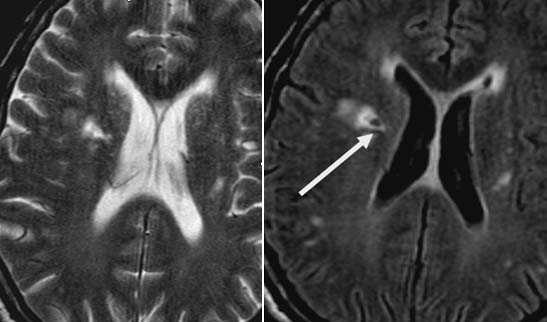

Первые часы ОНМК. Изменения в области правого островка демонстрирует только программа DW insult.

Бассейн кровоснабжения левой верхней мозжечковой артерии, острая стадия НМК.

Зона подострого ишемического НМК, в бассейне правой средней мозговой артерии. В режиме Т1 визуализируется симтом «вуалирования»- изоинтенсивность МР-сигнала.

Подострая стадия ишемического НМК. При внутривенном контрастировании определяется накопления КВ в бороздах на уровне зоны ишемии (гиральный тип усиления).

Зона хронического ишемического НМК, в бассейне левой задней мозговой артерии.

Ишемическое ОНМК, ствол мозга (подострый период)

Кортикальное ишемическое НМК

Лакунарное ишемическое ОНМК на фоне хронической сосудистой недостаточности.